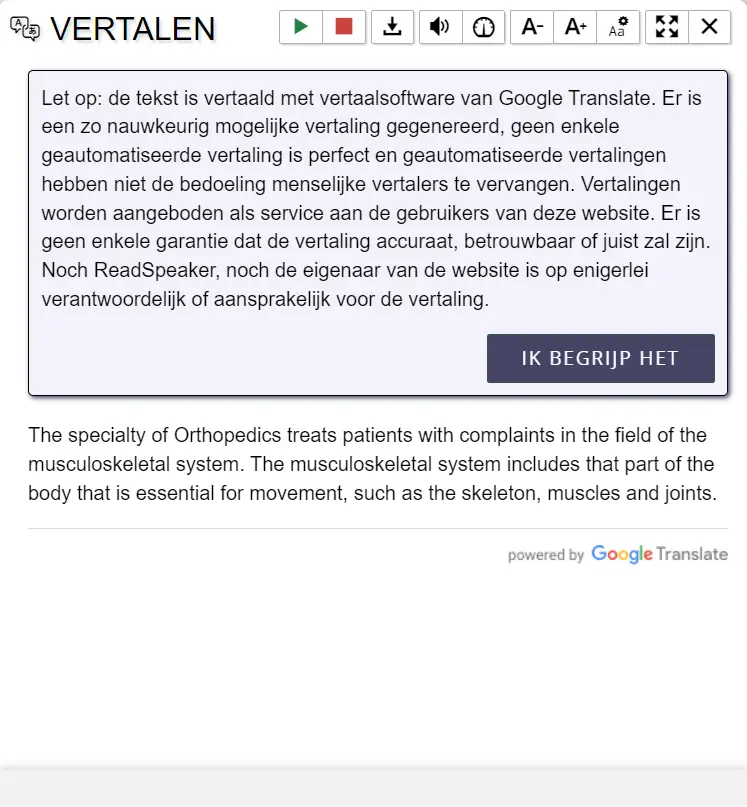

Bij een hielspoor is er sprake van overbelasting. De aanhechting van de peesplaat aan de onderzijde van de voet bij de hak is dan overbelast. Hielspoor is de meest voorkomende oorzaak van hielpijn.